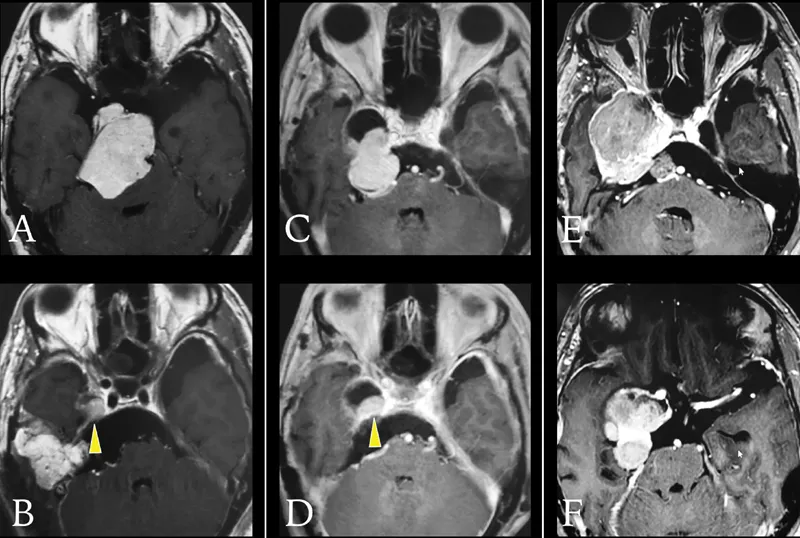

体格检查显示步态共济失调明显,左侧面部V2和V3分布区感觉明显...

这台手术由巴特朗菲教授主刀。虽然病灶周围紧邻面听神经、三...